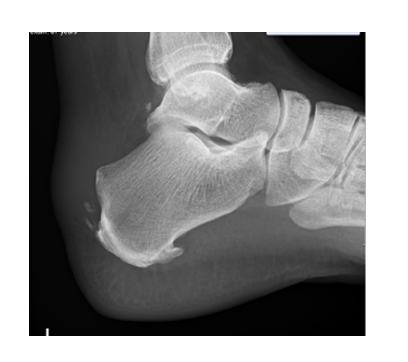

Haglund deformity:

A bony prominence on the back the heel with is often associated with a high angle of the heel bone. The prominent bony bump often irritates the bursa that sits over the bone.

There is no direct correlation between the size of the deformity and the degree of symptoms experienced.